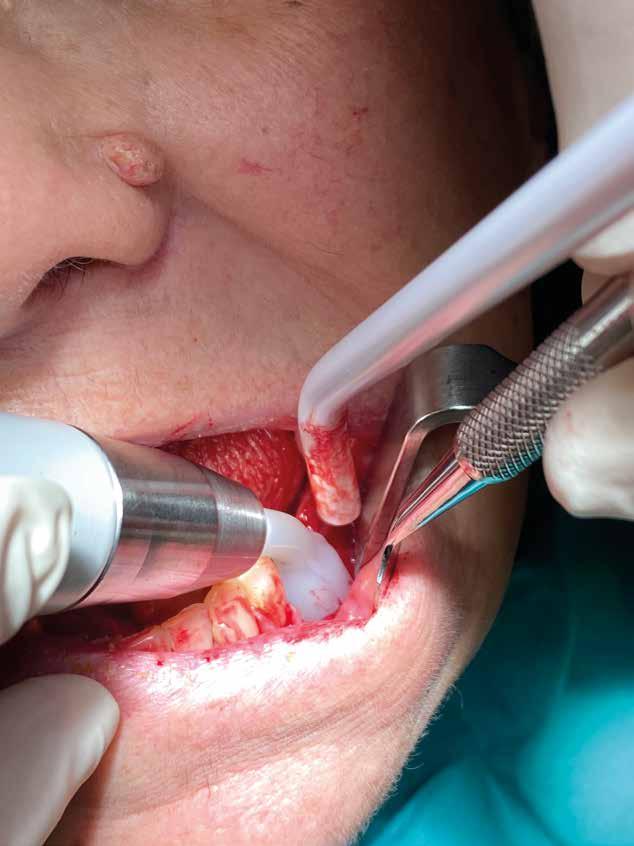

Esempio chirurgico di accesso tra 2 elementi dentari con conformazione della cresta alveolare ampia. Incisione del lembo in cre sta senza scarichi laterali con sollevamento di 2 lembi, palatale e vestibolare; si può notare come quest’ultimo non si estenda oltre

Estrazione di 3 elementi dentari complicata da frattura coronale di 2.4 e presenza di 2 corone protesiche unite su denti pluriradicolati. L’approccio deve prevedere la rimozione delle corone protesiche e la separazione delle radici, semplificando le manovre di estrazione e consentendo di risparmiare i tessuti molli pericoronali e prevenire la frattura

Il rispetto dei tessuti molli consente di ridurre i tempi di guarigione, sebbene a siti più ampi corrisponda un tempo di ripristino o maggiore. Il mantenimento delle corticali vestibolari, palatine e l’assenza di alveolite post-estrattiva riducono l’atrofia ossea.

Un ridotto scollamento dei tessuti molli riduce edema e dolore post operatorio, mentre la preparazione del sito implantare a bassi giri con irrigazione limita il trauma del tessuto osseo.

Una incisione lineare netta si estende coinvolgendo minimamente il dente mesiale e maggiormente in direzione distale, consente di evitare l’esecuzione di incisioni di scarico che provocano una interruzione della vascolarizzazione maggiore, senza ridurre la visibilità del campo operatorio.

Disegno del lembo d’accesso con spostamento della incisione crestale sul versante palatino. Lo scollamento della porzione vestibolare deve avvenire con uno scollatore di piccole dimensioni e l’ausilio di una pinza chirurgica